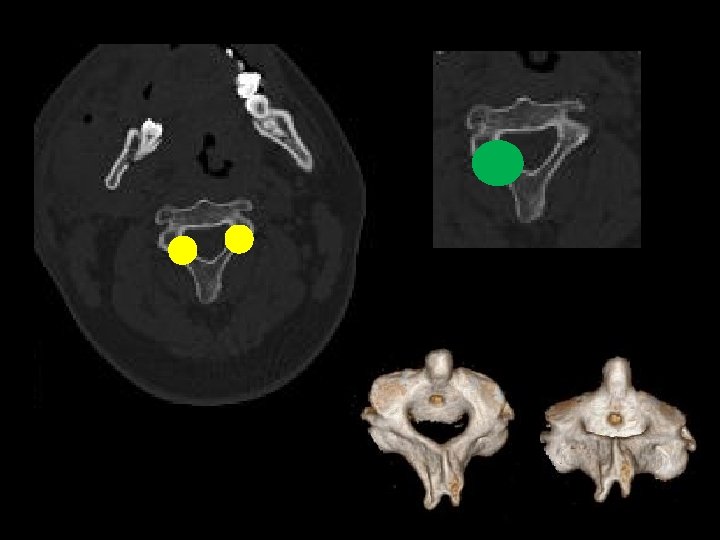

Son fracturas/ espondilosisis? ? Busquemos falsos !!

Diagnósticos diferenciales? ? ? Núcleos de osificación 2 darios Hendiduras/grietas (Clefts) Núcleos de Schmorl Limbus vertebra Improntas vasculares Malformaciones Oseas Artificios

Ejemplos! Arco anterior bipartito Arco posterior fusión incompleta Fx vs no fx !!

Fracturas vs nucleos de osificacion secundarios Ver: bordes irregulares vs bordes esclerosos y lisos!!!

Sitios de hendiduras!